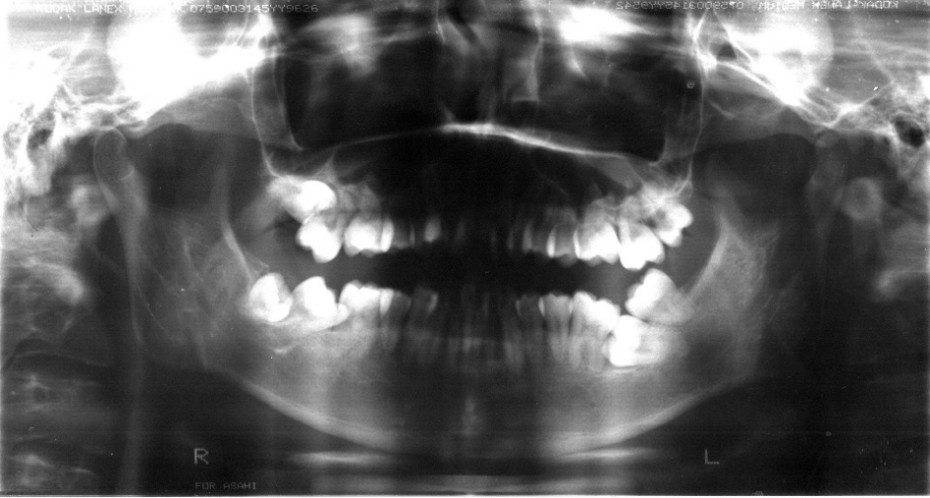

Before~After

下顎の奥歯に智歯(親知らず)が覆いかぶさっている状態を「重積状埋伏」といいます。

このような状態ではどうしたらよいかわからずに、抜歯が必要と考えてしまいます。しかし、必ずしも抜歯の必要はなく保存療法もあります。